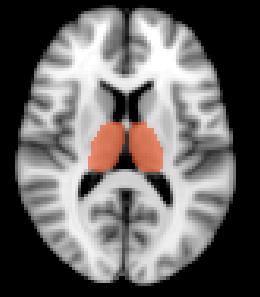

Advanced MRI biomarkers for MS progression

Changes in brainvolume are predictive of clinical and

disability status in CIS, RRMS, and PPMS